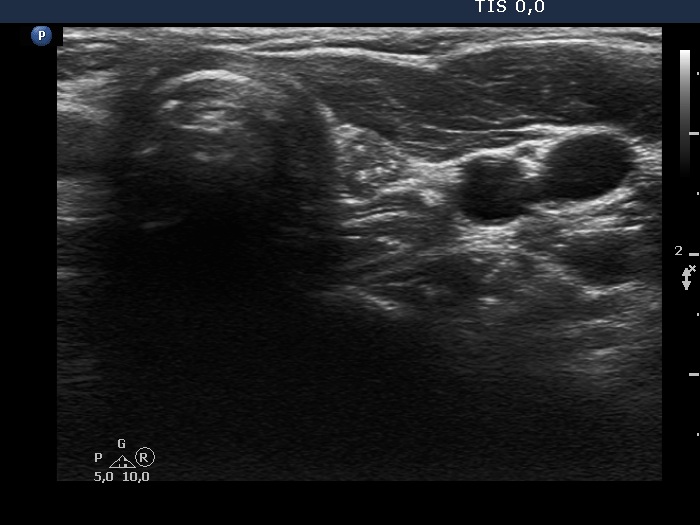

Ultrasonography. There was a hypoechoic lesion which had microcalcifications in the left thyroid bed. The dimensions were 5x5x7 mm.

Cytology resulted in papillary cancer.